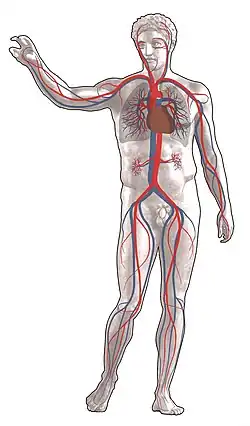

Angiologia é a especialidade médica que se ocupa do tratamento clínico das doenças que acometem vasos sanguíneos (artérias e veias) e vasos linfáticos,[1] como varizes, aneurismas e obstruções arteriais. Atua em conjunto com a cirurgia vascular que se ocupa do tratamento cirúrgico das ditas doenças.

As doenças arteriais incluem a aorta (aneurismas/dissecção) e as artérias que irrigam as pernas, mãos, rins, cérebro e intestinos. Também cobre trombose arterial e embolia; vasculites; e distúrbios vasoespásticos. Naturalmente, trata da prevenção de doenças cardiovasculares, como ataque cardíaco e derrame. As doenças venosas incluem trombose venosa, insuficiência venosa crônica e veias varicosas. As doenças linfáticas incluem formas primárias e secundárias de linfedema.